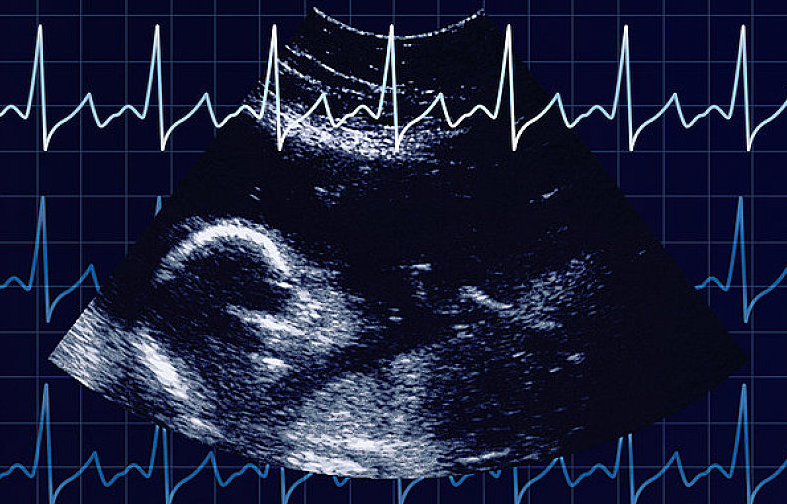

通過(guò)胎心監(jiān)護(hù)能了解到胎兒在子宮內(nèi)的情況,因此,孕媽們應(yīng)按時(shí)產(chǎn)檢,從孕32周(患有妊娠高血壓等疾病的孕媽從孕28周)開(kāi)始就要進(jìn)行胎心監(jiān)護(hù)。

當(dāng)各種原因引起胎兒缺氧時(shí),胎心很敏感地會(huì)出現(xiàn)變化。胎兒正常的胎心率為110~160次/分,正常的胎兒心率隨子宮內(nèi)環(huán)境的不同,時(shí)刻發(fā)生著變化,胎心率的變化是中樞神經(jīng)系統(tǒng)正常調(diào)節(jié)機(jī)能的表現(xiàn),也是胎兒在子宮內(nèi)狀態(tài)良好的表現(xiàn)。若胎心率分或>160次/分,持續(xù)10分鐘以上,稱(chēng)為胎心過(guò)緩或胎心過(guò)速。

由胎心率判斷性別是不正確的,胎心率的快慢跟胎兒在宮內(nèi)情況有一定的關(guān)系,如胎兒處于睡眠狀態(tài)是胎心率會(huì)慢一點(diǎn),胎兒活動(dòng)時(shí)會(huì)快一點(diǎn);缺氧時(shí)、有宮縮時(shí)、臍帶受壓了等等都會(huì)對(duì)胎兒心率造成影響。